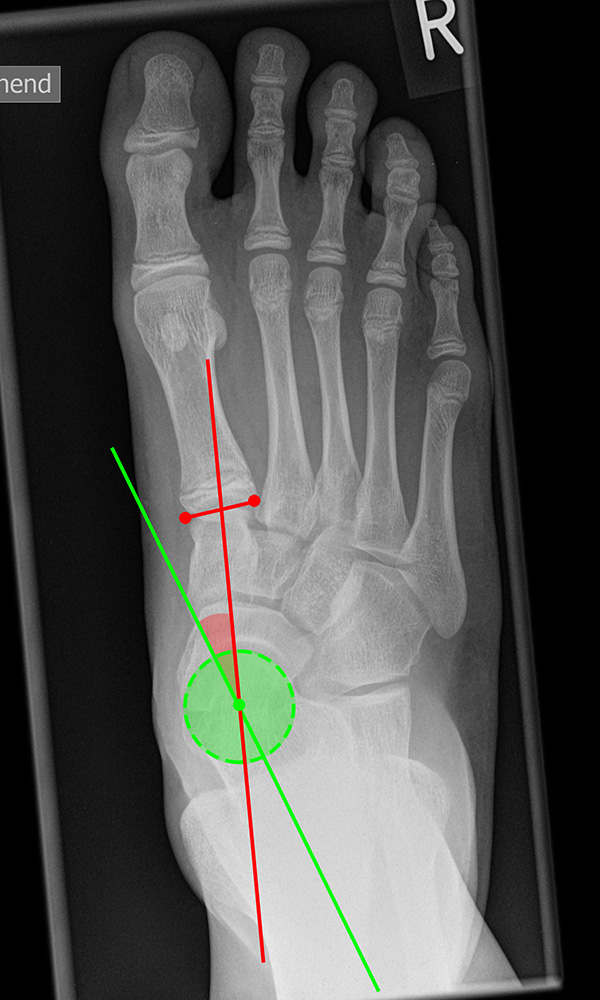

Vermessung der belasteten Aufnahmen des Fußes

Winkelmessungen am Fußskelett beziehen sich sämtlich auf belastete Aufnahmen 6. Die folgenden Aufnahmen zeigen die üblicherweise verwendeten Winkelmaße und ihre Definition. Viele Fehlstellungen des Fußes betreffen den Vor- und Rückfuß. Dies sollte bei der Beurteilung der Bilder und der Therapieplanung stets berücksichtigt werden.

Beurteilung von Fehlstellungen des Vorfußes

Zur Vollansicht und zum Lesen der Bildbeschreibung bitte die Bilder anklicken.

Gelenkflächenwinkel

DMAA (Distal metatarsal artikular angle, Syn. Gelenkflächenwinkel): Winkel zwischen der Achse des Os metatarsale I (rot) und dem Lot auf die distale Gelenkflächenebene (blau) des Os metatarsale I. Die Gelenkflächenebene (grün) wird definiert durch zwei Punkte, welche die mediale und laterale Begrenzung der Gelenkfläche definieren (Norm: <10° 5). Die Projektion des DMAA ist stark abhängig von der Rotation des Os metatarsale I 7. Daher ist bei der operativen Behandlung des Hallux valgus eine Beurteilung häufig erst nach Korrektur der Pronationsstellung des Os metatarsale I möglich. Tendenziell wird der DMAA auf präoperativen Röntgenaufnahmen überschätzt.

Beurteilung eines Metatarsus adductus

Medial wird eine Linie von der medialen Begrenzung des TMT1-Gelenks und der medialen Begrenzung des Talonavikulargelenks (TN) gezeichnet. Auf der lateralen Seite des Fußes wird eine zweite Linie von der lateralen Begrenzung des Calcaneocuboid-Gelenks (CC) zur lateralen Begrenzung des TMT5-Gelenks gezeichnet. Die Mittelpunkte beiden Linien werden verbunden (blau). Der Winkel zwischen der Achse des Os metatarsale II (rot) und dem Lot auf Verbindungslinie (grün) ist ein Maß für die Stellung des Vorfußes zur Fußwurzel. Dieser Wert dient zur Charakterisierung eines Pes adductus. Ein Pes adductus kann zu einem normwertigem Intermetatarsale I/II Winkel führen, obwohl klinisch eine ausgeprägte Hallux valgus Deformität vorliegt 8. (Norm: ±13° 9.

Meary’s angle dorsoplantar (Talo-Metatarsale-I-Winkel)

Der Talo-Metatarsale-I-Winkel wird auf den belasteten dorsoplantaren und lateralen Aufnahmen bestimmt. Es wird jeweils die Achse durch den Talushals gelegt (grün) und der Winkel zur Achse des Os metatarsale I bestimmt (rot). Der Winkel liefert keine Information darüber, an welcher Stelle sich die Fehlstellung befindet. Auch kann ein Serpentinen-Fuß „physiologische“ Werte liefern, da Os metatarsale I und Talushals parallele Achsen aufweisen, obwohl eine erhebliche Fehlstellung vorliegt 11. (Norm: 7,7 ± 8,2° 11).